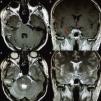

Los condromas craneales son tumores derivados de remanentes de células embrionarias condrocíticas que habitualmente aparecen en la sincondrosis de la base del cráneo. A diferencia del resto del organismo,donde los tumores condroides constituyen el tumor óseo primario más frecuente solo por detrás de los de estirpe hematopoyética, a nivel craneal constituyen una entidad poco frecuente con una incidencia de menos del 1% de los tumores intracraneales. Presentamos el caso de un varón de 42años remitido a nuestra consulta por el hallazgo de una lesión extraaxial situada en la región del cavum de Meckel y extensión a la fosa posterior con compresión del troncoencéfalo tras clínica de paraparesia de 6meses de evolución. Bajo el diagnóstico de un neurinoma del V par craneal se realiza una exéresis subtotal del tumor mediante un abordaje combinado supra-infratentorial presigmoideo. El resultado anatomopatológico postoperatorio confirma el diagnóstico de condroma craneal.

Cranial chondromas are tumours arising from chondrocyte embryonic remnants cells that usually appear in the skull base synchondrosis. In contrast to the rest of the organism, where chondroid tumours are the most common primary bone tumour just behind the haematopoietic lineage ones, they are a rarity at cranial level, with an incidence of less than 1% of intracranial tumours. The case is reported on a 42 year-old male referred to our clinic due to the finding of an extra-axial lesion located close to the Meckel's cave region, with extension to the posterior fossa and brainstem compression after progressive paraparesis of 6 months onset. With the diagnosis of trigeminal schwannoma, a subtotal tumour resection was performed using a combined supra-infratentorial pre-sigmoidal approach. The postoperative histopathology report confirmed the diagnosis of cranial chondroma.